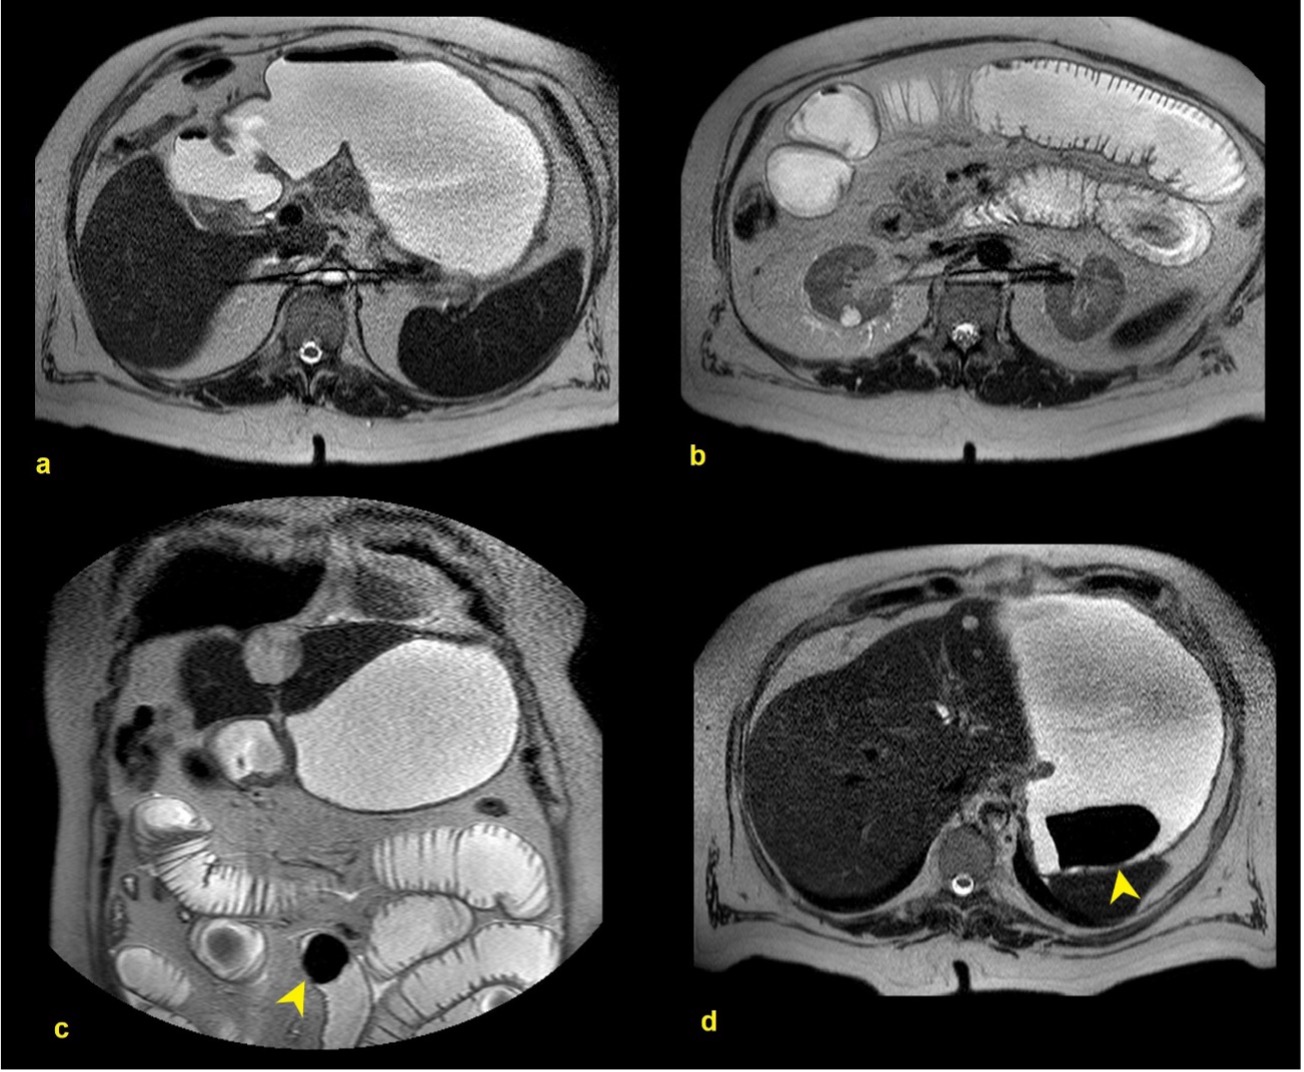

We present a case of a 65-year-old male that presented to the emergency department due to a 3-day history of vomiting and abdominal pain. He also complained of postprandial fullness, anorexia, and weight loss in the past 3 months. He had a history of cholelithiasis and was on the waiting list for cholecystectomy. On examination, he had a distended, tender abdomen in the upper quadrants and right iliac fossa. Laboratory test results showed a mild neutrophilic leukocytosis, anemia, and C-reactive protein of 3.99 mg/dL (normal range <0.5 mg/dL). Abdominal ultrasound performed in the emergency department showed multiple hypodense hepatic nodules, cholelithiasis without signs of cholecystitis and heterogeneous intragastric content. Subsequently, he performed a CT abdominal scan which showed large gallstones impacted in the duodenum, causing gastric outlet obstruction (Bouveret’s syndrome). It also suggested the presence of a cholecystoduodenal fistula (Figure 1). No dilation of small bowel loops or any intraluminal content was identified. He was admitted for additional study. For better characterization of the liver lesions, an abdominal MRI was performed, characterizing the liver nodules as hemangiomas. Also, several dilated fluid-filled small bowel loops could now be observed, and a large gallstone was found in the ileum, suggesting migration of one of the previously identified in the duodenum on the initial CT scan. In the stomach, another gallstone could be identified. (Figure 2). Esophagogastroduodenoscopy showed one large black stone of 6-7cm in the distal antrum. The patient underwent an exploratory laparotomy with intra-abdominal examination, and two stones were identified, one at the gastric level and the other at the distal ileum, close to the ileocecal valve. Gastrolithotomy and enterolithotomy were performed with stone removal. The patient recovery was unremarkable.

Figure 2: T2-weighted axial (a, b, d) and coronal (c) images of an MRI performed one week later. No gallstones were identified in the duodenum (a). Instead, several dilated fluid-filled small bowel loops could now be observed (b). Even though the MRI did not include the pelvis, the cause of the obstruction was a large gallstone that was found in the ileum (c, arrowhead). Another gallstone could be observed in the stomach (d, arrowhead).